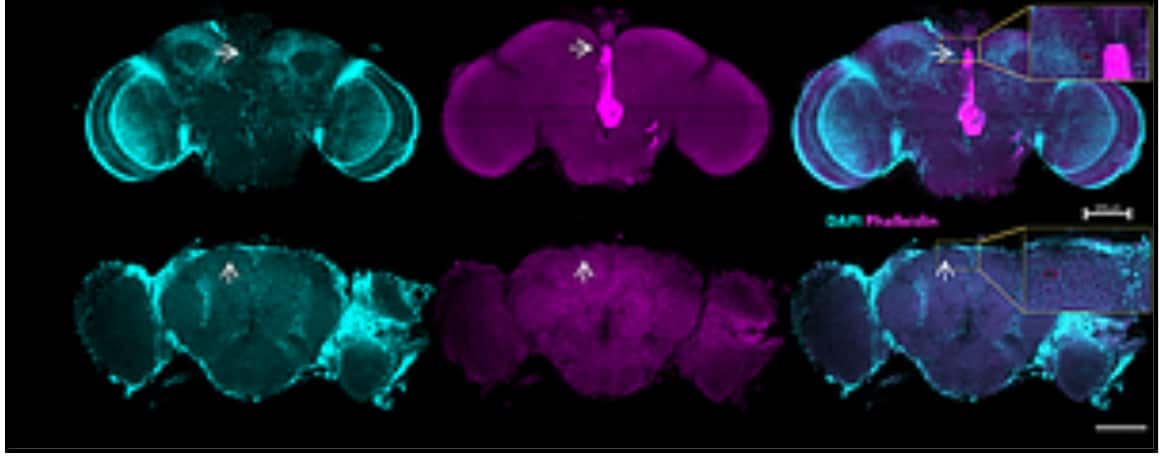

صورة مجهرية: في الصف العلوي - صورة لدماغ ذبابة طبيعية، وفي الصف السفلي - دماغ ذبابة مصابة بالتنكس العصبي، يظهر فيه وجود ثقوب في الدماغ. حقوق الصورة: شاي كلوكسي